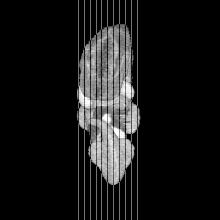

MRI Slice Selector

Mouse: click on a line below to select a view

Finger: tap a line below with a very light touch